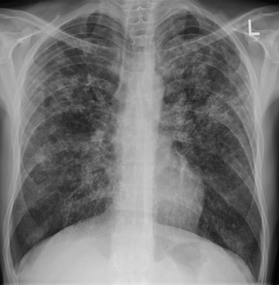

Tuberculosis creates cavities visible in x-rays like this one in the patient's right upper lobe.

In active pulmonary TB, infiltrates or consolidations and/or cavities are often seen in the upper lungs with or without mediastinal or hilar lymphadenopathy.[1] However, lesions may appear anywhere in the lungs. In HIV and other immunosuppressed persons, any abnormality may indicate TB or the chest X-ray may even appear entirely normal.[1]

2. Any cavitary lesion - Lucency (darkened area) within the lung parenchyma, with or without irregular margins that might be surrounded by an area of airspace consolidation or infiltrates, or by nodular or fibrotic (reticular) densities, or both. The walls surrounding the lucent area can be thick or thin. Calcification can exist around a cavity.